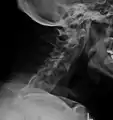

X-rays

The earliest changes demonstrable by plain x–ray shows erosions and sclerosis in sacroiliac joints. Progression of the erosions leads to widening of the joint space and bony sclerosis. X-ray spine can reveal squaring of vertebrae with bony spur formation called syndesmophyte. This causes the bamboo spine appearance. A drawback of X-ray diagnosis is the signs and symptoms of AS have usually been established as long as 7–10 years prior to X-ray-evident changes occurring on a plain film X-ray, which means a delay of as long as 10 years before adequate therapies can be introduced.[25]

Lateral X-ray of the neck in ankylosing spondylitis